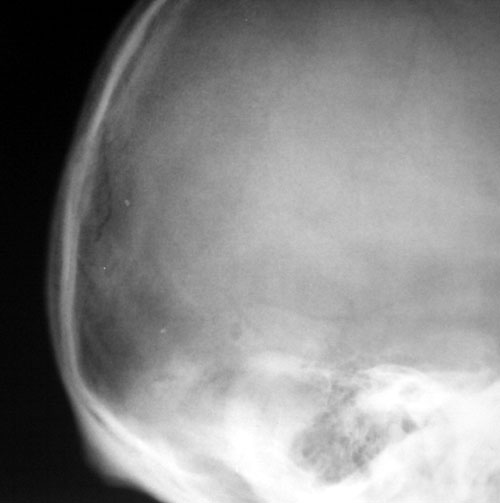

标题: X1067:[原创]头颅硬物击伤

看看这个是否骨折?

我觉得颅骨枕部线性骨折,因为无论颅缝还是血管压迹,总会有周缘的硬化,可是它似乎没有,请各位老师指教

我觉得颅骨枕部线性骨折,因为无论颅缝还是血管压迹,总会有周缘的硬化,可是它似乎没有,且边缘锐利.建议ct检查.

支持8楼除线型骨折外还要警惕凹陷骨折。请作ct检查

这是一张侧位片 应和正位片结合对照观察 如实在不放心只有做ct 了